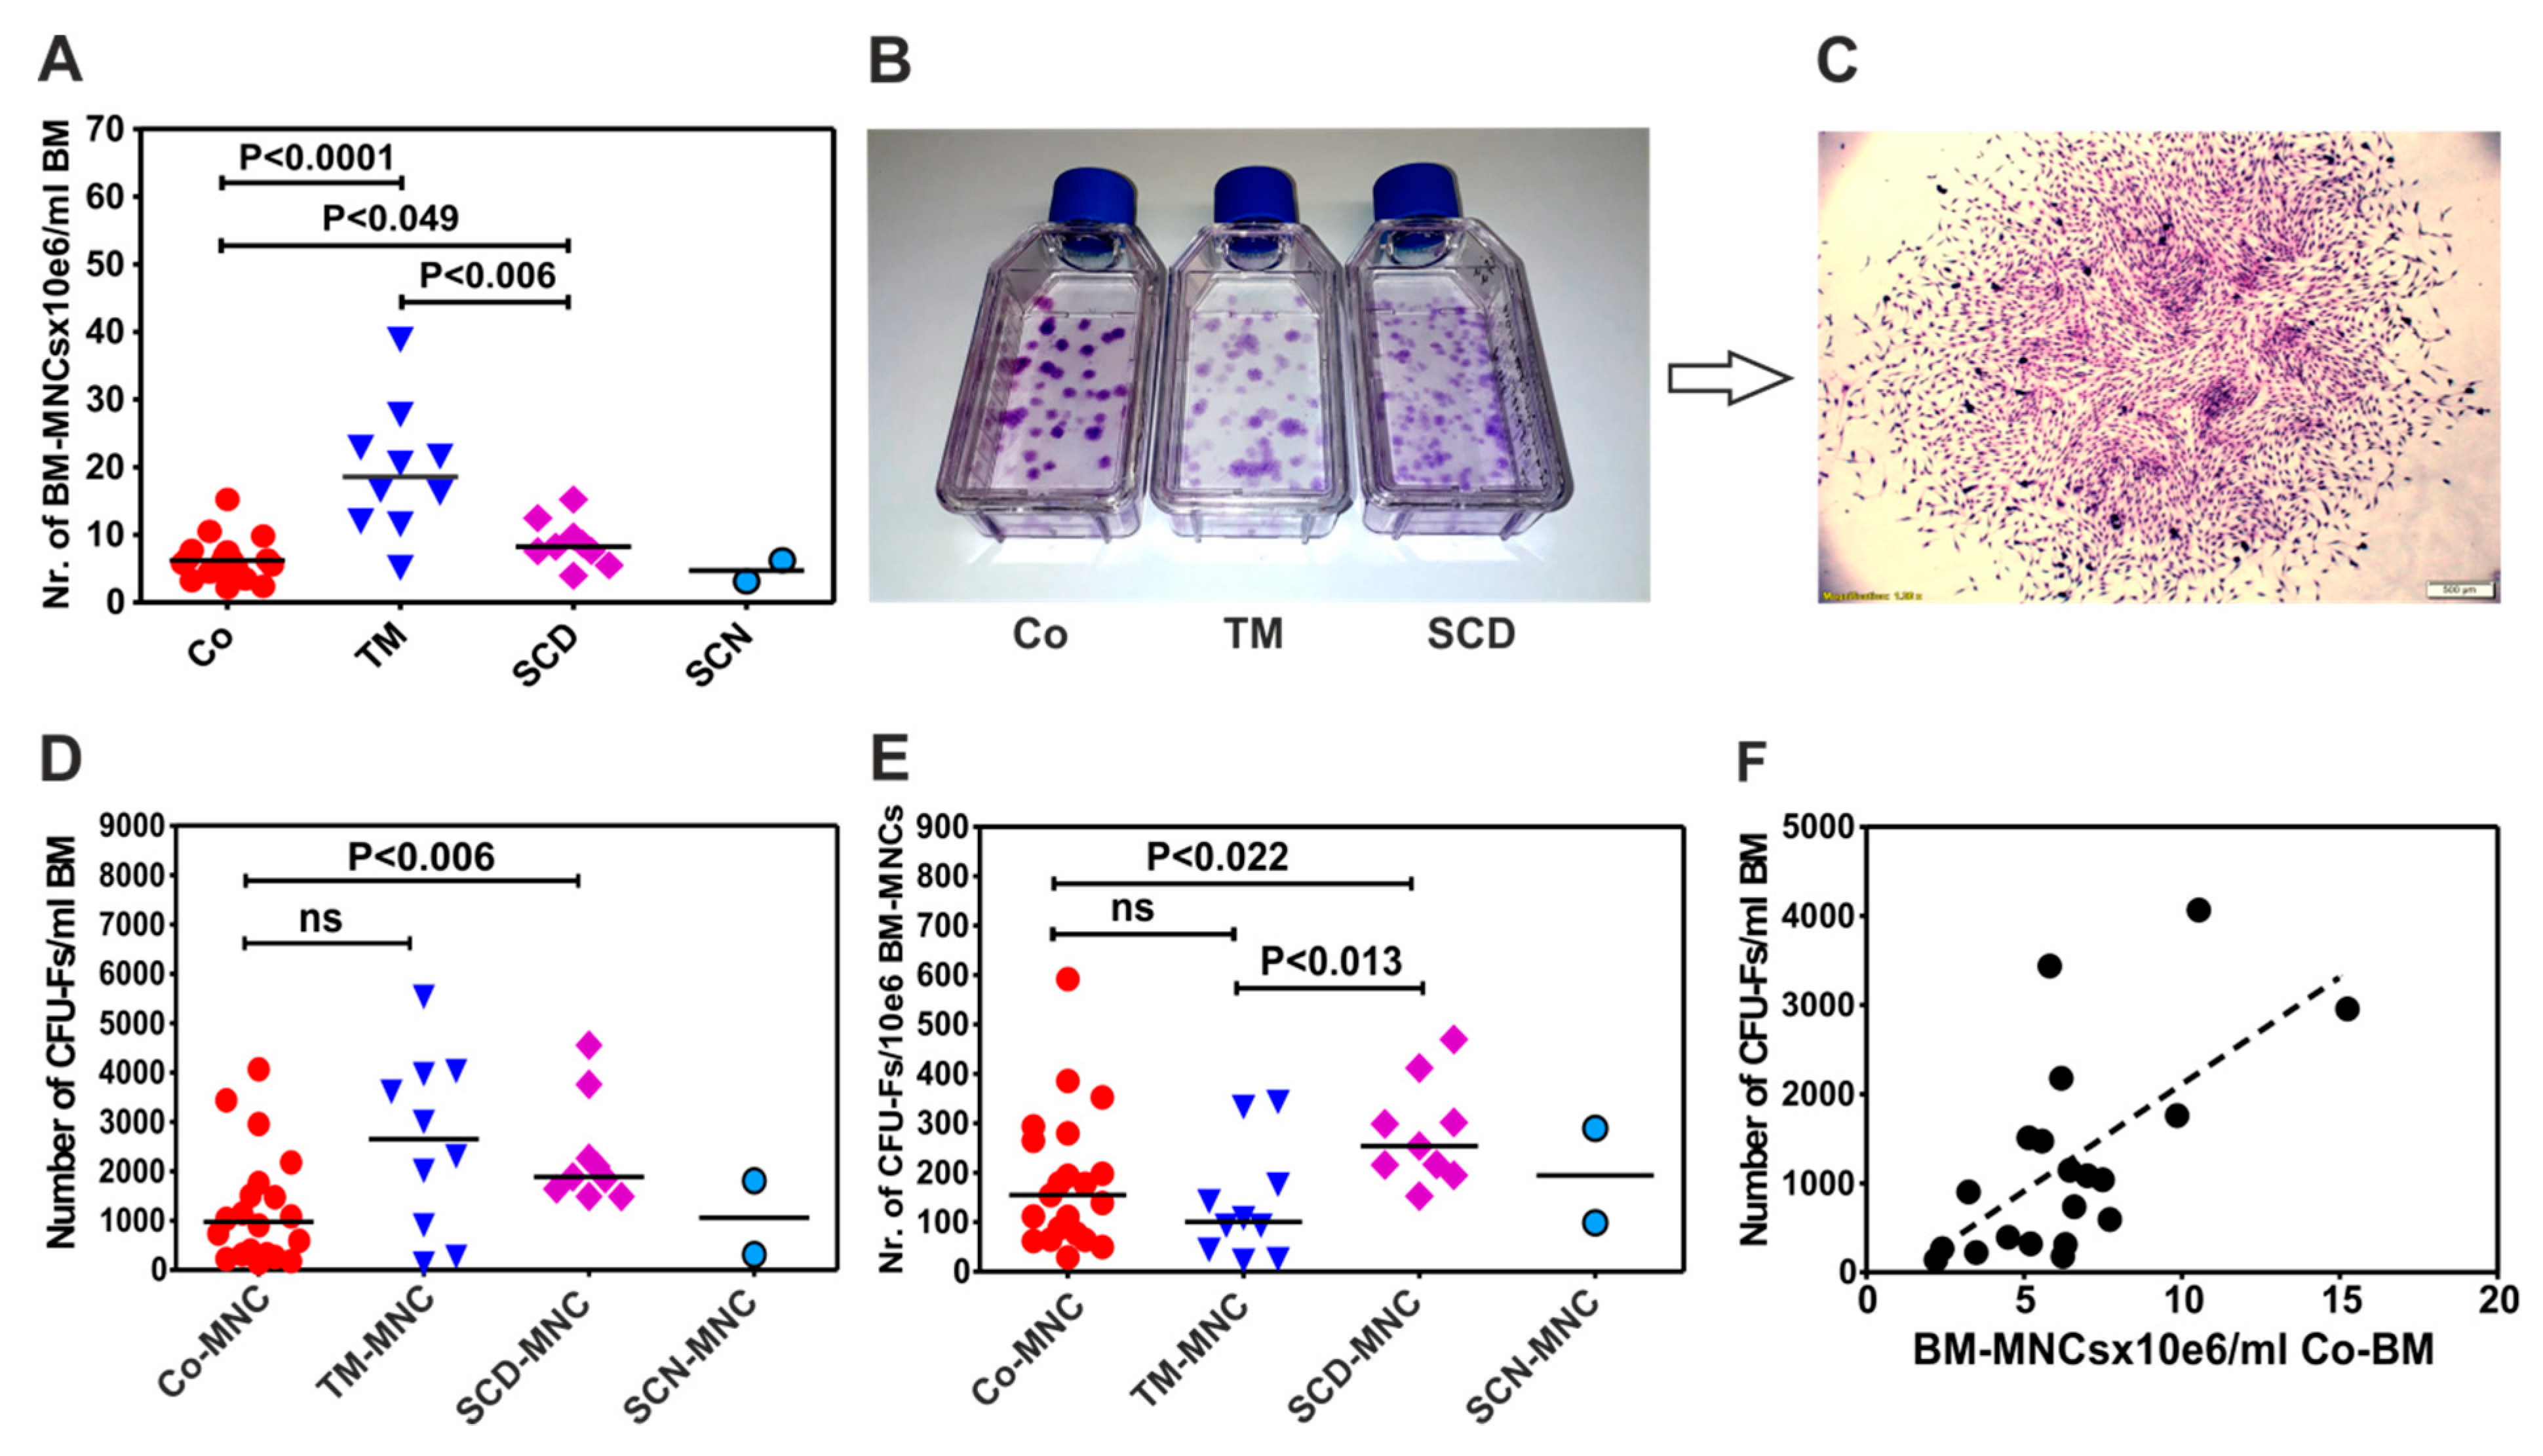

3.1. Patients with Thalassemia Contain more BM-MNCs per Milliliter Bone Marrow than Patients with Sickle Cell Disease (SCD) and Control Group

3.2. BM-MNCs of Patients with SCD Generate More CFU-Fs per 1×106 BM-MNCs Compared to Patients with Thalassemia or Healthy Donors

3.3. BM-MNCs of Patients with NMHD Demonstrate a Normal Generation and Proliferation Potential of Mesenchymal Stromal Cells (MSCs)